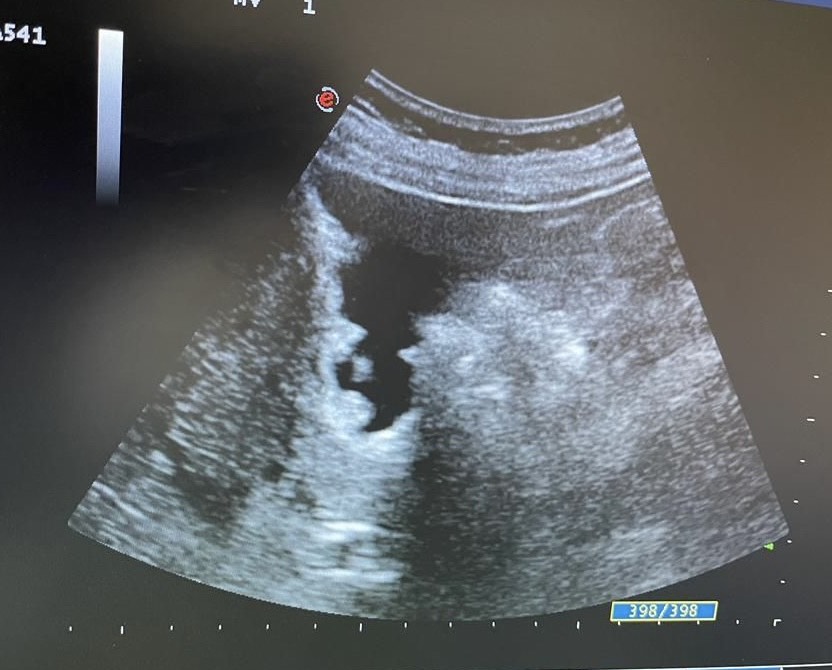

Mentalmente describí las lesiones, se trata de lesiones múltiples hiperecogénicas y adheridas a la pared vesicular y que no producen sombra posterior.

Confirmé que no se trataba de colelitiasis sino que en mi opinión eran múltiples pólipos vesiculares y alguno de ellos cercano a 1 cm de diámetro, sin poder descartar malignidad con la ecografía, por lo que solicité un TC abdominal que informó de un único pólipo vesicular de 6 mm.

Desde la consulta de cirugía se solicitó ecografía reglada y control en 6 meses que informó de múltiples engrosamientos nodulares en relación con pólipos (más de 10), los de mayor tamaño alcanzan 9 mm de grosor máximo. Alitiasica.